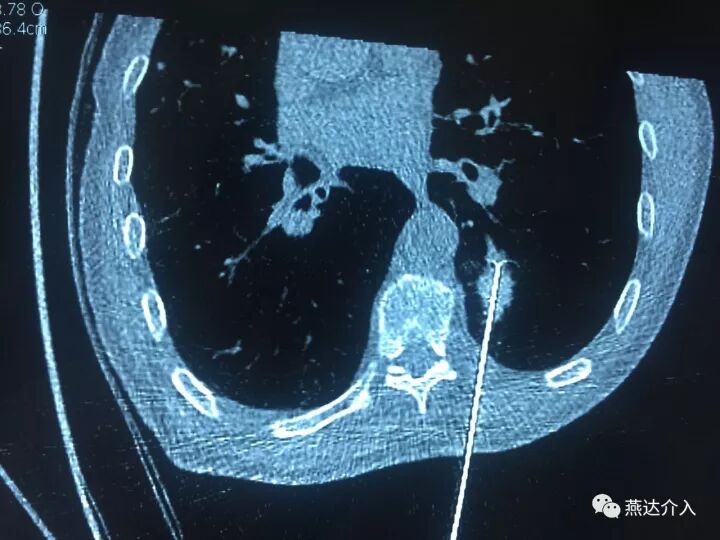

近日燕达医院收治一名肺内占位患者,行PET-CT考虑肺内占位,恶性可能,肺部多发小结节,考虑转移。为进一步明确肺内占位性质,放射介入科予患者穿刺活检,病理证实为肺鳞癌。为治疗肿瘤,决定予患者行肺癌射频消融术。

术中予患者2cm射频针3针消融,术后可见病灶周围晕征出现,肿瘤内可见消融后气化影,消融效果全面完全,术后患者情况良好,无不适。